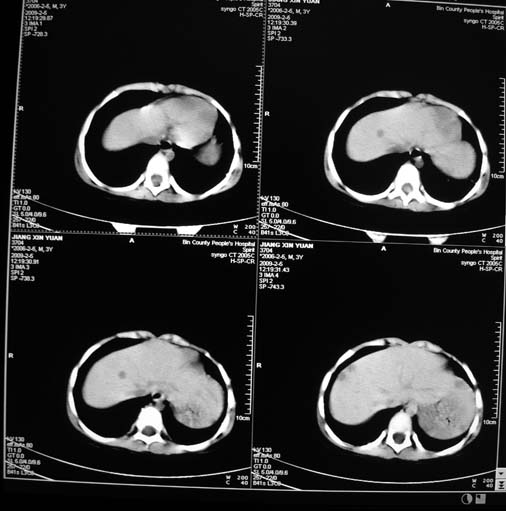

男,3岁,肾母细胞瘤术后,肝脏的低密度是什么?

胰尾下方见两枚囊形灶,肠管?病灶?左侧肾上腺区见团块状影,转移病灶?术后表现?建议与前片对比,肝脏病灶好像有牛眼表现,不除外转移,如果不增强,建议加做个b超,至少可分清其囊性或者实性,又便宜,免费自已给他弄一下也行,对诊断有帮助

左肾母细胞瘤术后,多发性转移可能性大。

左肾母细胞瘤术后:肝脏多发低密度灶,考虑转移可能性大。

左肾母细胞瘤术后:肝脏多发低密度灶,考虑转移可能.请结合临床及增强以及术前检查等